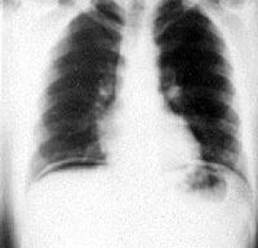

X-ray examination of abdominal cavity organs for presence of free gas (pneumoperitoneum, fig. 17).

Figure 17 – X-ray examination of abdominal cavity, pneumoperitoneum